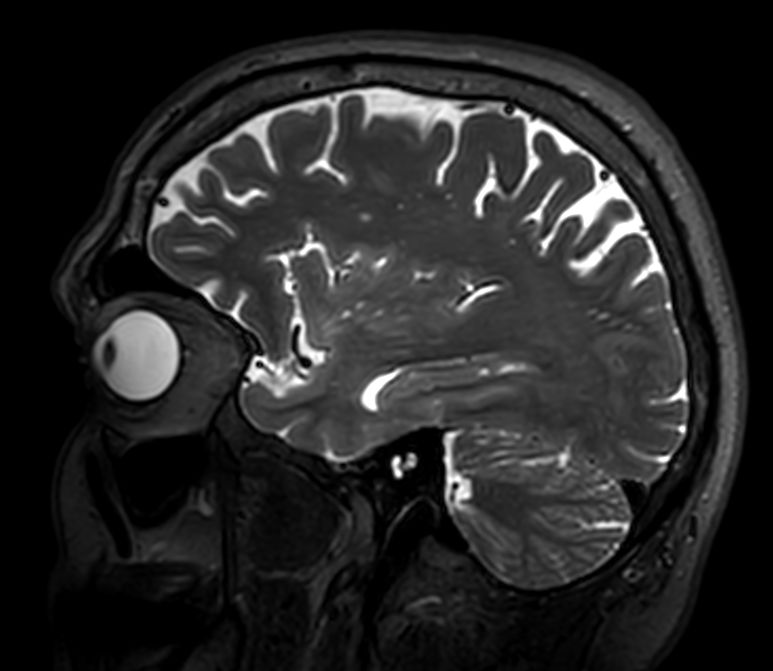

Sagittal 3D VIEW - T2w FLAIR